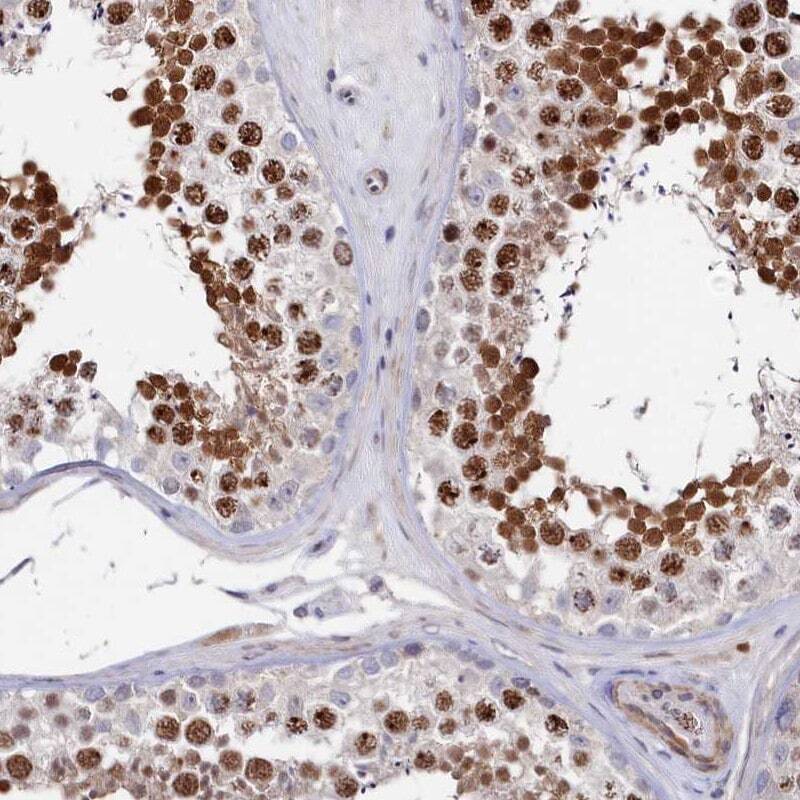

Supportive validation

- Submitted by

- Invitrogen Antibodies (provider)

- Main image

- Experimental details

- Immunohistochemical analysis of TIGD4 in human testis using TIGD4 Polyclonal Antibody (Product # PA5-57351) shows strong nuclear positivity in cells in seminiferous ducts.